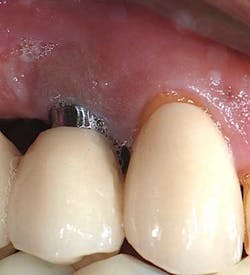

The following is a case example of a patient who presented with an ailing implant No. 5 diagnosed with advanced peri-implantitis. Tooth No. 6 was also involved with severe periodontitis. An argument could have been made to extract both the implant and the tooth and try to replace the area with another two implants after grafting or a fixed partial denture. Both options may have left the patient with severe ridge defect that would have needed to be treated with either pink ceramic or multiple attempts at regeneration. With new, improved biomimetic technology, both the implant and the tooth were saved.

This is a 62-year-old African American male with a medical history positive for GERD. He takes Nexium. He was referred for an ailing implant No. 5 with a PD of 15+ mm as well as a PD of 15+mm on adjacent natural tooth No. 6. Upon initial presentation, suppuration exuded from the sulcus of No. 5i and No. 6. The surgery was as follows:

- Patient presented back to our office with 3-4 mm probing depth and now has a stable result for not only the tooth but also the implant